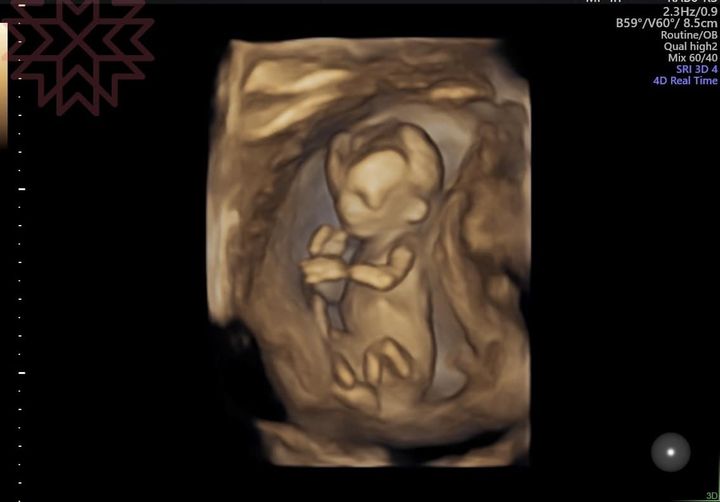

星期五 星期五 輕鬆一下 昨天 這個寶寶 感覺就像是Stacey Kent拿著麥克風在我耳邊輕柔的唱著 I Wish I Could Go Travelling Again 我 也該去旅行了吧 FB原文討論串 分享此文: 分享到 X(在新視窗中開啟) X 分享到 Facebook(在新視窗中開啟) Facebook 喜歡 正在載入... 相關 發表留言 取消回覆 Δ